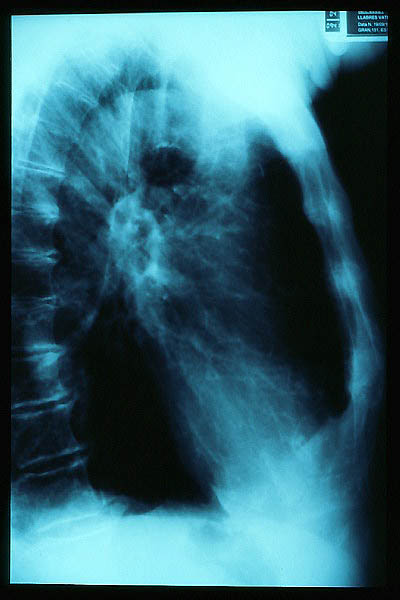

TBC pulmonar antigua